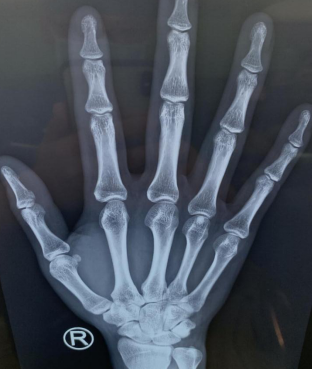

两天后,刘某感觉右手拇指疼痛加重、活动受限,于是来到betway在线登陆。手外科四病区收治后,拍片检查看不出来鱼刺具体位置,只能根据刘某的描述,拆除右手伤口缝线,延长伤口,在大概2厘米的位置终于找到了鱼刺,原来鱼刺藏在了桡腕关节囊内。

术前CT